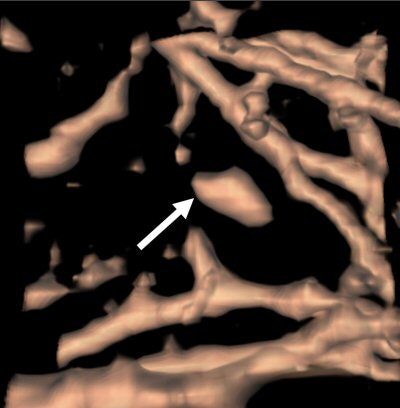

| An elongated nodule missed by all three radiologists during free search. On the axial image (above), the small nodule looks more likely to be a vascular structure with an elongated shape and parallel orientation with adjacent branching vessels. On the coronal image (below), the lesion seems more globular in the craniocaudal direction. 3D volume-rendered image (bottom) presents a discrete nodule between vessels. Although this true-positive nodule was detected by CAD, all three radiologists rejected this nodule with low confidence scores. All images courtesy of Dr. Chin Yi. |

![]() |